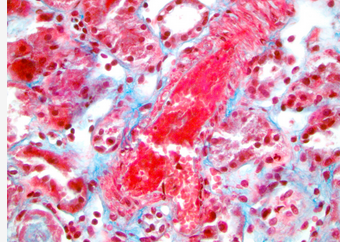

This patient has evidence of lung, kidney, and hematologic involvement with evidence of bleeding, as well as arterial and venous thrombosis all occurring within days. Additionally, she is anti-β2 glycoprotein I antibody positive and has histopathological evidence of vessel occlusion. The histopathology slide images from renal biopsy demonstrate a thrombosed small artery surrounded by renal tubules (Figure 2) and an arteriole at the base of a glomerulus with thrombosed glomerular capillaries (Figure 3).

Thrombotic microangiopathy (400× magnification). Histology image courtesy of Dr. Bruce Jones of Henry Ford Hospital, Detroit, MI, USA.